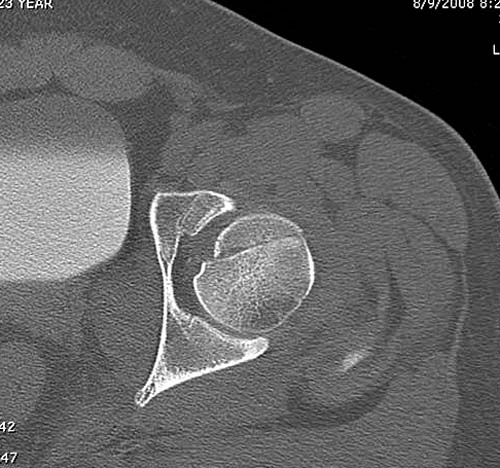

Представлены несколько вариантов фиксации: первый случай перелом головки с задним краем, операция из заднего доступа Кохер, а второй случай изолированный перелом головки - из трохантерного доступа.

Имя     : 2 Fem head  CT.jpg

Тип     : image/jpg

Размер  : 42793 байтов

Описание: отсутствует

Url     : http://weborto.net:8080/pipermail/ortho/attachments/20111231/d311d17a/attachment-0011.jpg